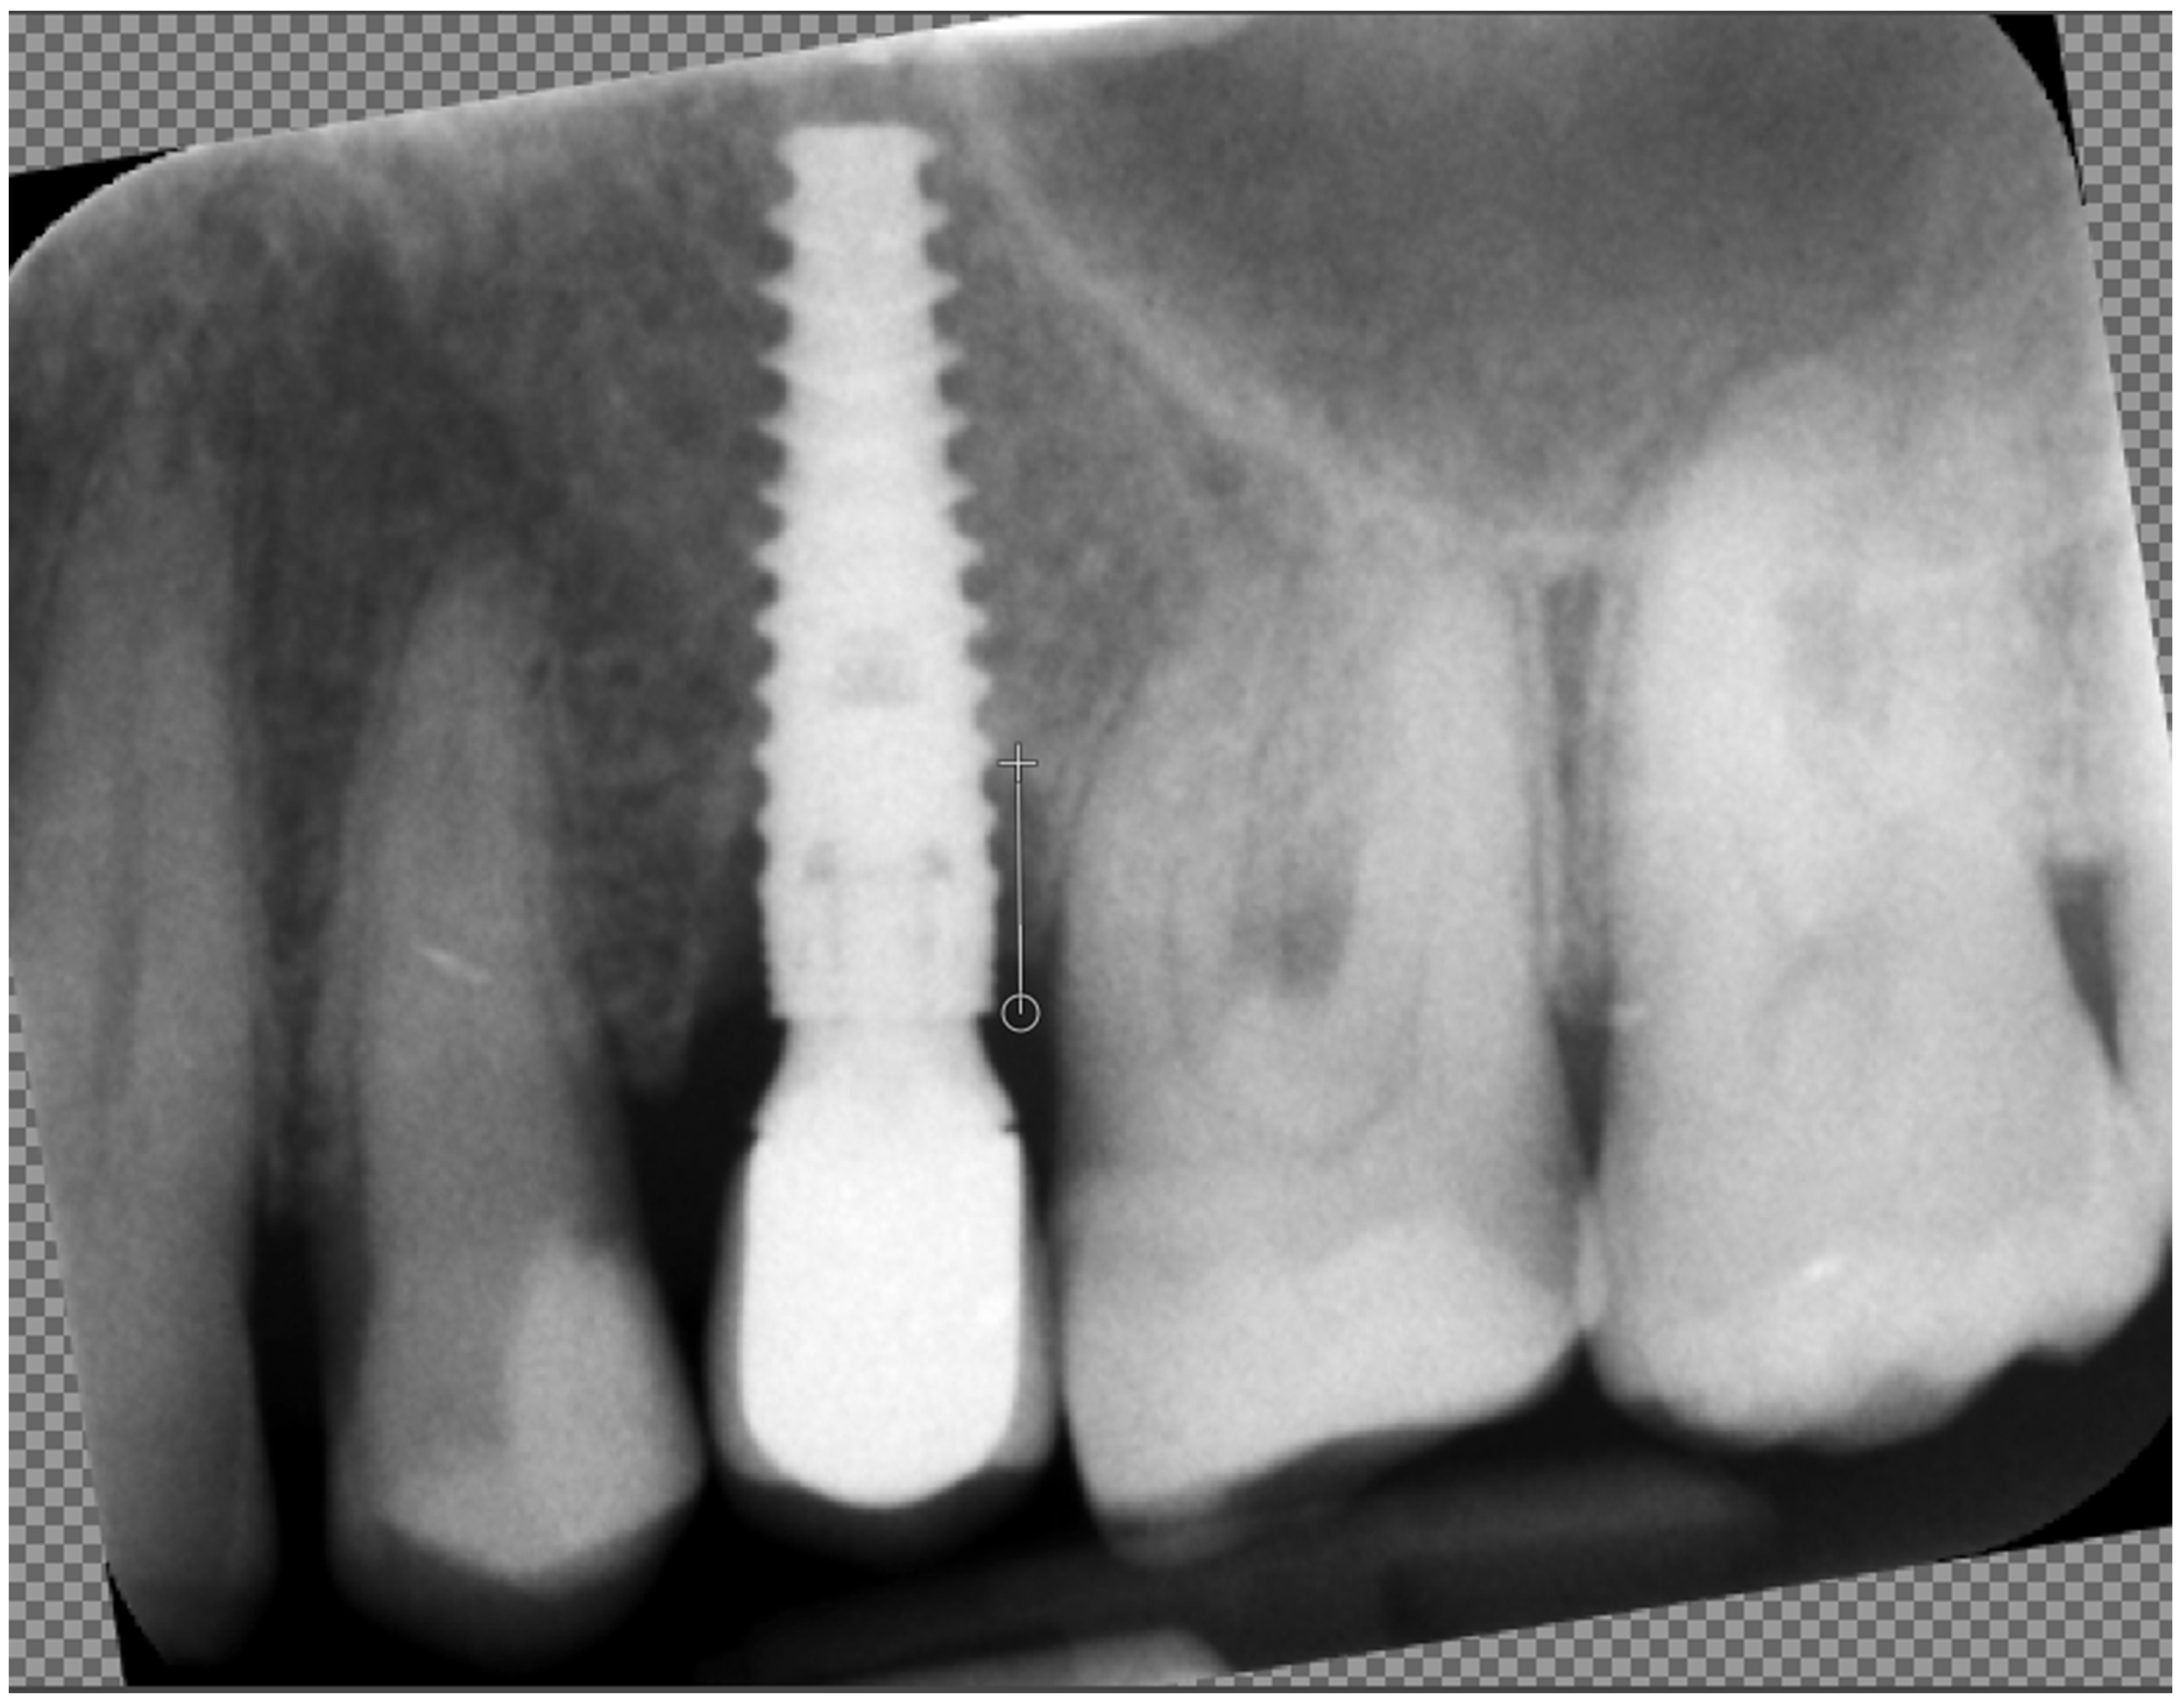

- The CI must be calculated on a defined Region of Interest (ROI) on the radiograph, and this ROI selection must be standardized. In our study, we standardized the ROI based on the method described by Kozakiewicz et al. [10], ensuring that the measurements are reliable and reproducible.